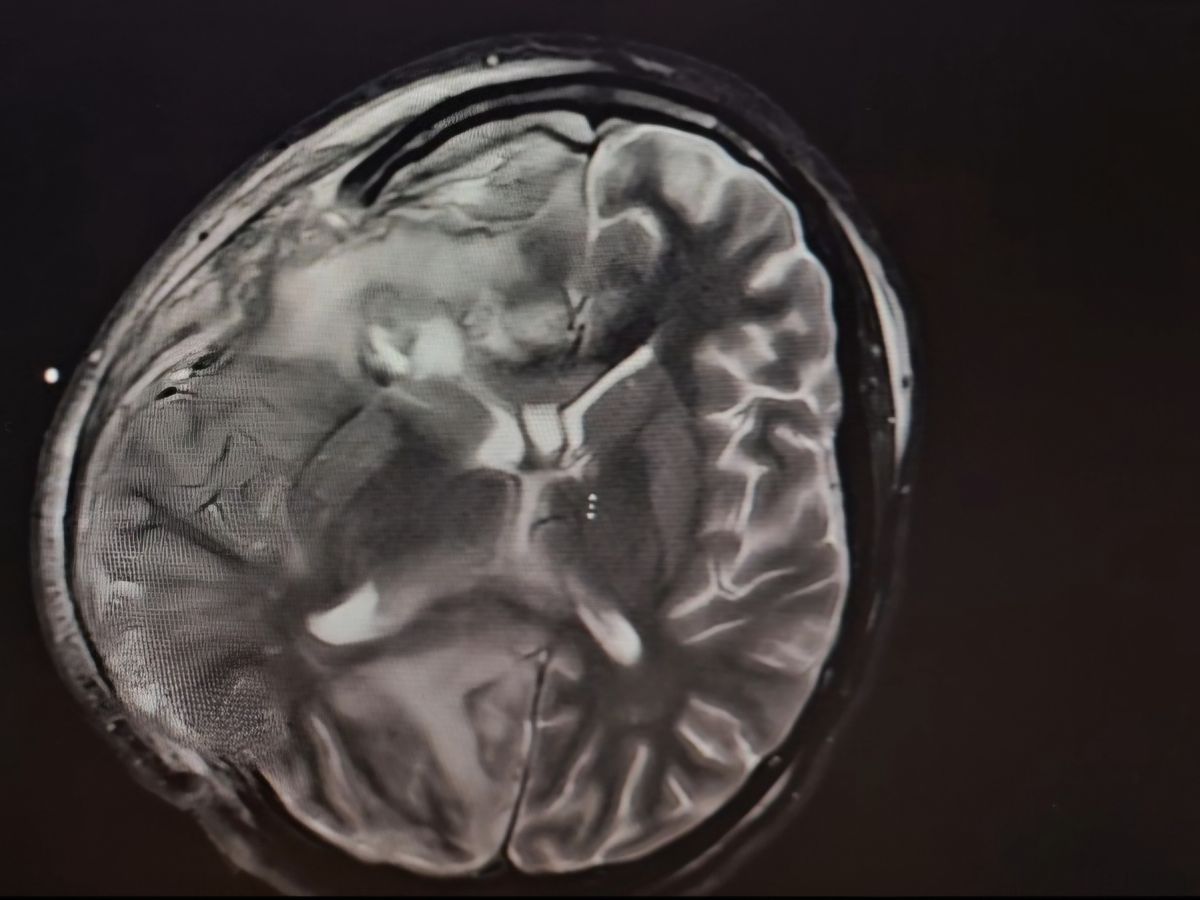

It all began with what seemed like a routine sinus infection, but quickly escalated to a life-threatening condition. The infection spread to the right side of her brain, causing serious complications. Alejandra is now nonverbal and unable to move the left side of her body, requiring multiple surgeries and ongoing medical care.

Her condition has been a constant rollercoaster of ups and downs, with moments of hope followed by heartbreaking setbacks. The infection has been diagnosed as a brain abscess, linked to Streptococcus intermedius—a rare and dangerous bacteria that has left her in a fragile state. The medical team is doing everything they can, but Alejandra’s prognosis remains uncertain, and her recovery journey will be long and difficult.